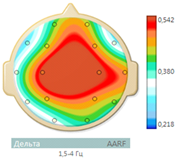

Electroencephalogram (EEG) showed epileptiform activity. An irregular alpha rhythm with a peak frequency of 10.5 Hz is recorded on the patient's EEG. The frequency-spatial structure of the alpha rhythm is pathologically distorted. The structure of the maximum values of average coherence is represented as a triangle in fronto-central departments, which is characteristic of an active epileptic process. A moderate increase in low diffuse beta and theta activity is noted. Against this background, in the left frontotemporal region, epileptiform activity in the form of spikes is recorded in large numbers, the frequency of which reaches 30 per minute. Rare discharges of high, sharp, bilaterally synchronous alpha waves with a frequency of 1-2 per min (Figure 1 & 2).

Figure 2 The maximum values of the mean coherence are presented in the form of a triangle in the frontal-central regions.